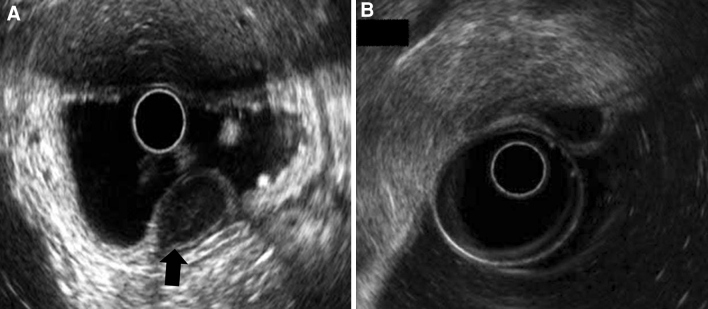

EUS was performed with a radial-scanning echo endoscope (Olympus GF-UM2000, 6 MHz and 12 MHz; Olympus Optical Co.) to assess the layer of origin. Other features that were identified by EUS included the growth pattern (intragastric vs. extragastric), the demarcation of margin, and the degree of the connection area (narrow vs. wide) with the fourth layer of the tumor. A narrow versus wide muscular connection was defined as a connection area with the fourth layer that was ≤50 versus >50 % of the maximal diameter of the tumor base, respectively (Fig. 1) [11].

Fig. 1.

The degree of muscular connection with a subepithelial tumor as shown by endoscopic ultrasound. A Narrow muscular connection with the tumor: the diameter of the connection with the fourth layer of the tumor is <50 % of the maximal diameter of the tumor base (black arrow hyperechoic demarcation line between the tumor and the muscularis propria layer). B Wide muscular connection with the tumor: the diameter of the connection with the fourth layer is >50 % of the maximal diameter of the tumor base